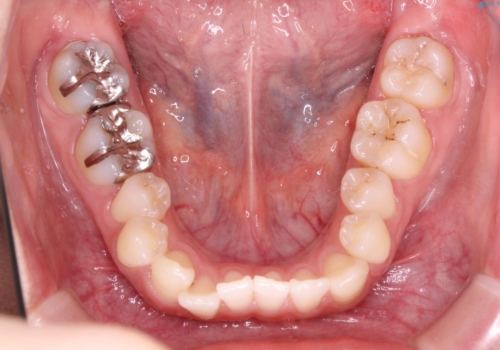

初診時の歯並びの状態としては、上下ともに前歯部の中等度のがたつきがあり、特に左上の前歯が1本内側に入り込んでしまっている状態でした。

抜歯なし/インビザラインによるマウスピース矯正にて治療を行いました。